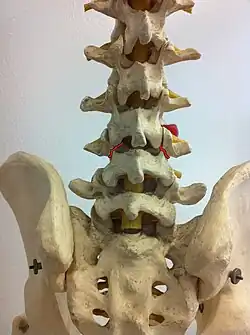

Spondylolysis is a bony defect or fracture within the pars interarticularis of the vertebral arch in the spinal column. The vast majority of spondylolysis occur in the lumbar vertebrae, however it can also be seen in cervical vertebrae.[3] The lumbar vertebra consist of a body, pedicle, lamina, pars interarticularis, transverse process, spinous process and superior and inferior articular facets, which form joints that link the vertebrae together. When examining the vertebra, the pars interarticularis is the bony segment between the superior and inferior articular facet joints located anterior to the lamina and posterior to the pedicle. Separation of the pars interarticularis occurs when spondylolysis is present in the spinal column.[14]

The scottie dog sign It was once used as a diagnostic sign in x-rays, for lumbar spondylolysis, but it is not commonly in use nowadays because of the advent of more sensitive diagnostic methods such as the CT scan and MRI scan. If spondylolysis is present, the pars interarticularis, or the neck of the dog, gives the appearance of a Scottish Terrier with a collar around its neck.[7]